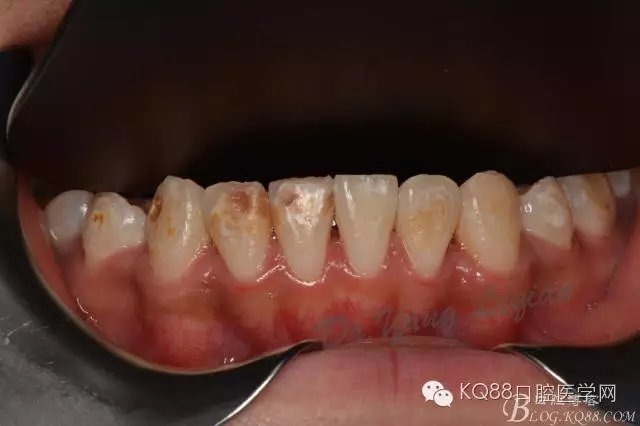

小美女今年16歲,正畸結(jié)束后下前牙唇側(cè)齲壞嚴(yán)重,影響美觀??紤]到患者年齡較小,所以和家長商量后決定現(xiàn)行樹脂貼面暫時修復(fù),待成年后重新制定修復(fù)計(jì)劃。

圖片由助理拍攝,比較雜。31只是做了拋光沒有做貼面。齲壞脫礦位置質(zhì)地較軟,小球鉆仔細(xì)去除,硅膠車針拋光。